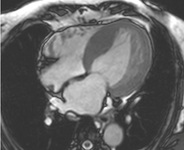

Ressonância nuclear magnética cardíaca (RNMC) de paciente com infiltração amiloide cardíaca. Após injeção de contraste de gadolínio, na fase tardia há um anel basal subendocárdico no ventrículo esquerdo (imagem de eixo curto basal)

Do acervo de Dr Jessica Webb; usado com permissão